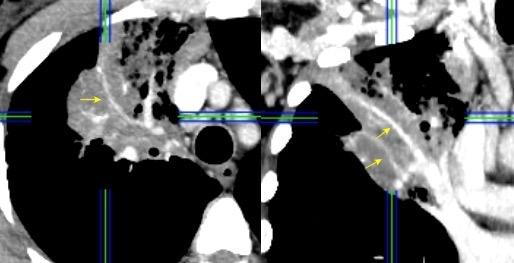

BRONCOGRAMA “OSCURO”

SIGNO DEL (dark bronchus sign)

Visualización de un bronquio más oscuro que el parénquima que le rodea.

VIH+. Neumonía Neumocistis y Klebsiella

Se debe a la presencia de consolidación sutil en vidrio deslustrado.

(Signo de la silueta)

Se ha descrito en casos de neumonía por Pneumocystis jirovecii

Yadav P et al. The 'dark bronchus' sign: HRCT diagnosis of Pneumocystis carinii pneumonia. Ann Thorac Med. 2007

Gruden JF et al . High-resolution CT in the evaluation of clinically suspected Pneumocystis carinii pneumonia in AIDS patients w ith normal, equivocal or nonspecific radiographic findings. AJR 1997

MiniP